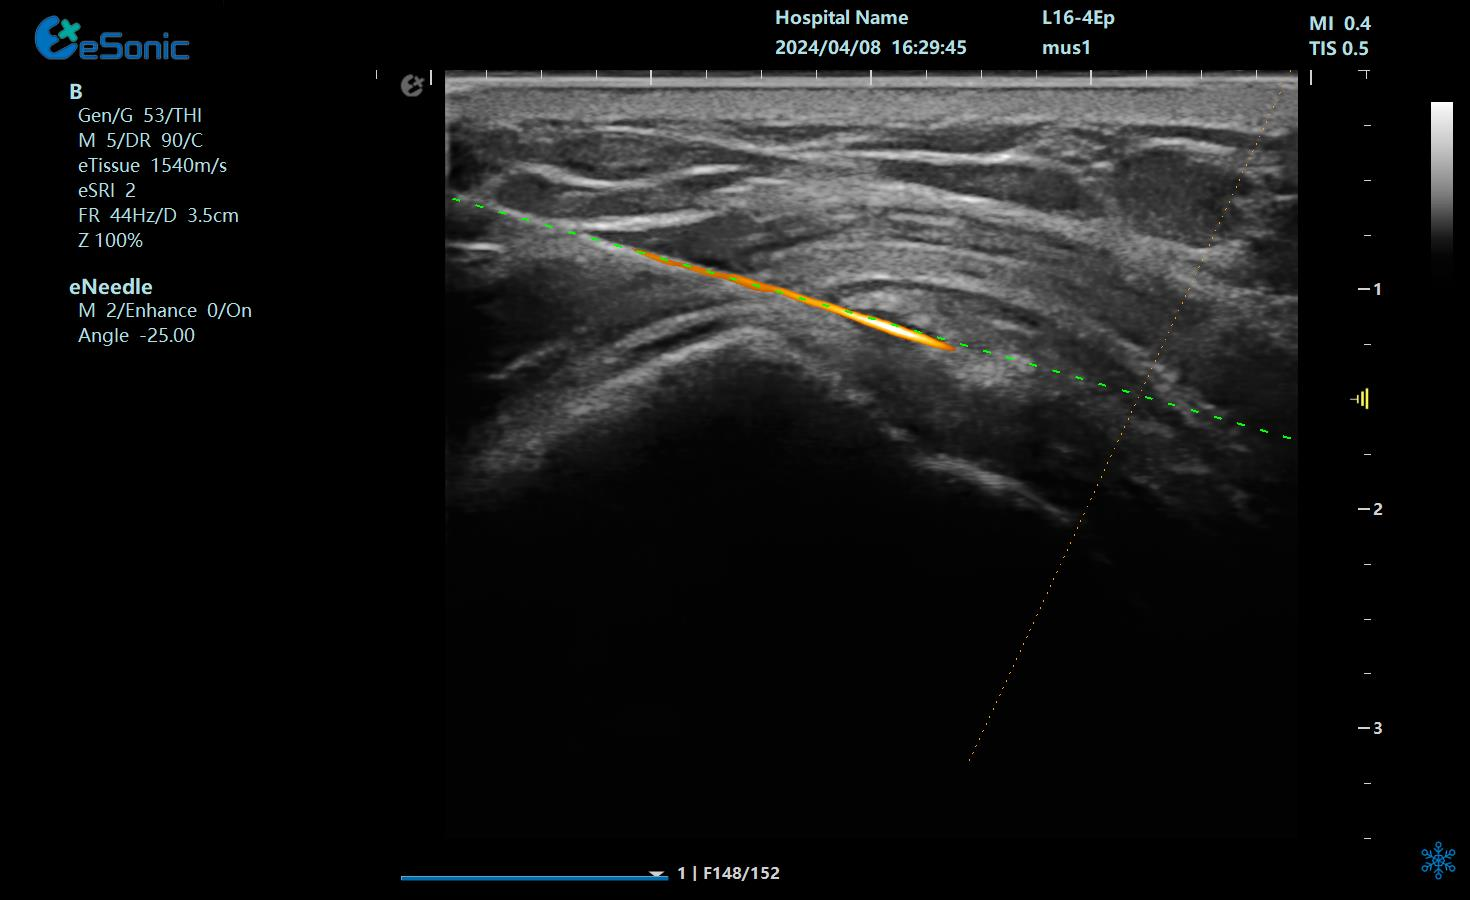

针针5.png

治疗中使用穿刺针智能Map和无磁导航技术